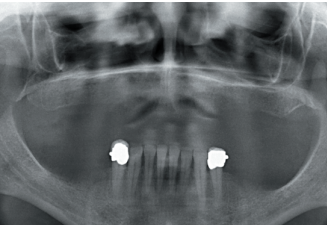

To start the diagnostic phase, a panoramic radiograph is performed that gives us an idea of the general condition of both jaws to start the treatment plan.

It shows that there is apparently some height in the maxillary ridge both anterior and posterior and a low dental nerve in the jaw that allows us to have a greater residual bone crest available for the insertion of the implants (Figure 3).

Subsequently, we proceed to perform a dental cone beam that offers a more accurate view of the type of implant rehabilitation that can be proposed. In the sections corresponding to the upper maxilla, there are areas where the direct insertion of the implants can be performed such as those corresponding to 16 and the central incisor zone of this quadrant (Figures 4-5) or in the second quadrant the area of the 27.

implant rehabilitation that can be proposed. In the sections corresponding to the upper maxilla, there are areas where the direct insertion of the implants can be performed such as those corresponding to 16 and the central incisor zone of this quadrant (Figures 4-5) or in the second quadrant the area of the 27. On the other hand, in the area corresponding to teeth 21 and 23 there is a significant horizontal atrophy, with a residual bone width of approximately 3.5 mm in the middle zone of the crest, with an enlargement in the most basal area of the same and conservation of both corticals. This leads to choose a split crest technique, in this case in two phases to achieve a greater final width and correct the inclination of the final implant as much as possible to achieve adequate aesthetics in the final prosthesis (Figure 6).

In the areas corresponding to teeth 11 and 13 the horizontal atrophy is even more marked. There is no trabecular bone separating the two corticals (vestibular and palatine) and the width is less than 2mm in some areas which is why block grafts are planned in this area. Short implants are planned in the mandible by direct insertion, and the area corresponding to the mandibular branch will be the donor area for the block grafts.